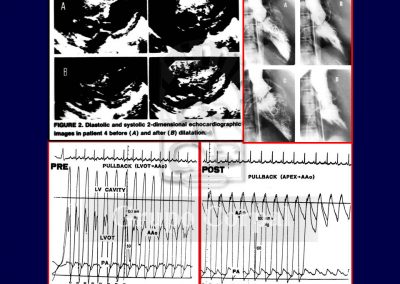

En 1985, por primera vez en el mundo, nuestro grupo describió una forma diferente de tratamiento mecánico para quitar la obstrucción subvalvular (Referencia). Si la membrana es fina, sin componente muscular, la membrana puede ser rota o rasgada mediante dilatación con catéter balón. El procedimiento es sencillo y eficaz en la desaparición de la obstrucción fija subvalvular, teniendo incluso efectos beneficiosos sobre la válvula aórtica, que deja de sufrir el chorro de presión en cada latido. Si la actuación es precoz, su historia natural mejora, al quitar el estímulo constante de la hipertensión intraventricular para el desarrollo de hipertrofia. Aunque este tratamiento es también paliativo, como la cirugía, en una enfermedad con carácter progresivo, su recurrencia a lo largo de 25 años es del 15%, pudiendo ser redilatada con los mismos efectos si es necesario.

Nuestro grupo ha efectuado estudios de seguimiento a largo plazo de pacientes así tratados que han demostrado una gran efectividad siempre que la selección de pacientes sea adecuada, con una membrana fina y sin componente muscular. (Referencias…)